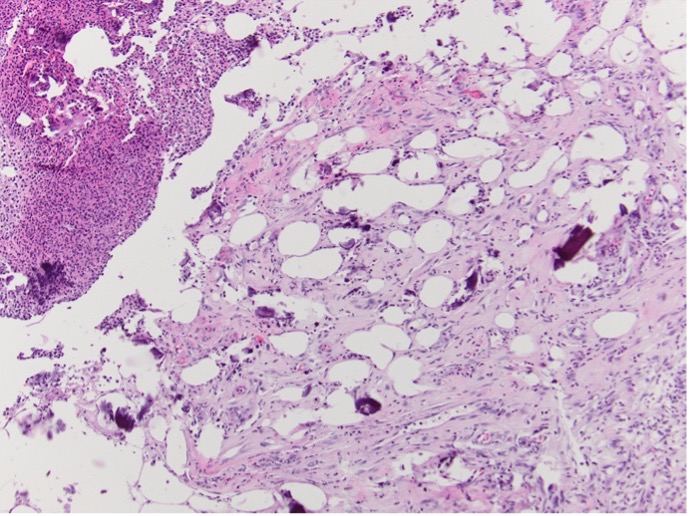

Three months prior to this current admission for worsening pain, she was hospitalized for the second time for recurrent MSSA bacteremia related to her chronic leg wound. At the time of her second admission, a biopsy of her ulcer was performed (Figure 1), which was reviewed at the time of her current admission (Figure 2).

Figure 1. Ulceration extends into the panniculus. Calcification is noted (Hematoxylin-eosin-stained sections; original magnification x100).